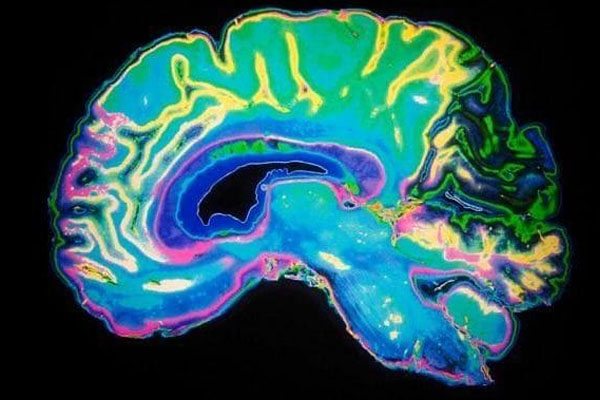

ولاحظ الباحثون انه حين يتخذ المتطوعون قراراهم تُفعَّل منطقة من الدماغ اسمها "العقد القاعدية" تقوم بدور حاسم في فهم قيمة الأشياء. واظهر التصوير بالرنين المغناطيسي ان نشاط هذه الشبكة من الدماغ يكون أكبر بكثير حين يكسب المتطوعون المال بإيذاء أنفسهم وليس إيذاء آخرين في مؤشر الى ان المال المكتسب بهذه الطريقة يكون غريزياً أعلى قيمة.

كما كشف البحث ان المنطقة التي ترتبط باصدار الأحكام الأخلاقية في الدماغ ، أي القشرة الجبهية الجانبية ، تكون في ذروة نشاطها حين يسفر الحاق الأذى عن قدر أدنى من الربح. وتبين الاختبارات ان هذه المنطقة تتواصل مع العقد القاعدية حين يرفض الأشخاص تحقيق ربح من إيذاء الآخرين.

واظهر التصوير بالرنين المغناطيسي ان القشرة المخية هي المنطقة الوحيدة من الدماغ التي تُفعَّل حين يفكر الشخص في مساعدة آخرين.